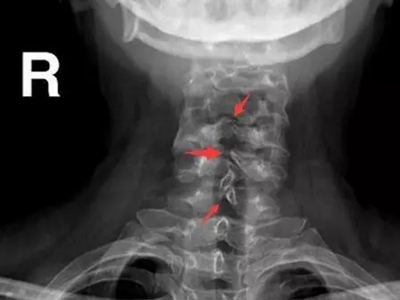

隐性脊柱裂颈部拍片见到骨头变形交错排列图

隐性脊柱裂的颈部在拍片检查时,可以见到颈部脊椎棘突、椎板未正常融合对接,颈椎排布交错变形,失去正常规律,这一般是多种因素导致脊柱发育畸形的结果。